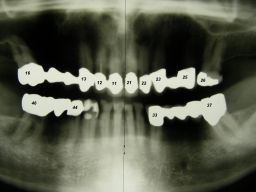

Das etwas dunkle Röntgenbild links(6/2003) zeigt diverse Probleme. Hier interessiert, daß der Zahn 22 (sprich: "zwei", "zwei") am 28.10.05 Schmerzen bereitete, weil der Zahnnerv unter Eiterbildung abgestorben war. Es brauchte 3 medikamentöse Einlagen, bis der Zahn ruhig war und am 18.11.05 eine Wurzelfüllung und einen Titanstift in den Wurzelkanal bekommen konnte. Bei der anschließenden Röntgenkontrolle rechts fiel der schlechte Randschluß der Krone 22 auf. |

Weil auch die anderen Schneidezahnkronen (12-22) durch Randreparaturen und den schlechten Randschluß erneuerungsbedürftig aussahen, wurden 4 Einzelkronen geplant. Vorher hieß es aber noch, die schlechte Wurzelfüllung im Zahn 12 (Röntgenbild links) besser zu machen. Hierfür wurden am 17.2.06 die alten Kronen 11 und 12 entfernt. Rechts das Bild nach Entfernung von alten Füllungen und Karies. | |